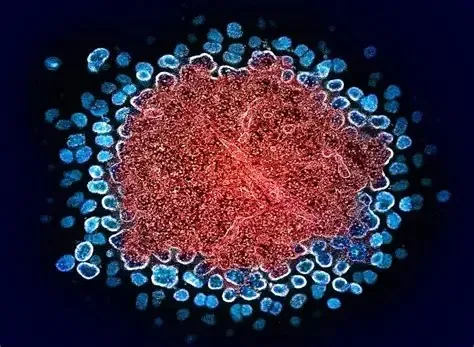

CAFÉ PODE REDUZIR A CHANCE DE DEMÊNCIA, DIZ ESTUDO

CAFEZINHO DO BEM 25/02/2026 - 10h03

CAFÉ PODE REDUZIR A CHANCE DE DEMÊNCIA, DIZ ESTUDO Beber de duas a três xícaras de café ou chá cafeinado por dia pode reduzir em cerca de 20% o risco de demência, aponta um estudo que acompanhou mais de 130 mil pessoas por 40 anos.